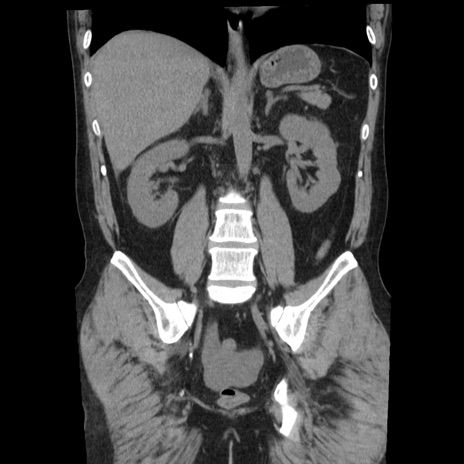

横断像

【症例】40歳代男性

【現病歴】2日前から胃痛あり。徐々に周期的な激痛に変化した。本日になっても激痛があるため受診。

【身体所見】意識清明、BT 38-39℃台あり、腹部:膨満、やや硬、右下腹部に圧痛あり。

【データ】WBC 8500、CRP 23.26